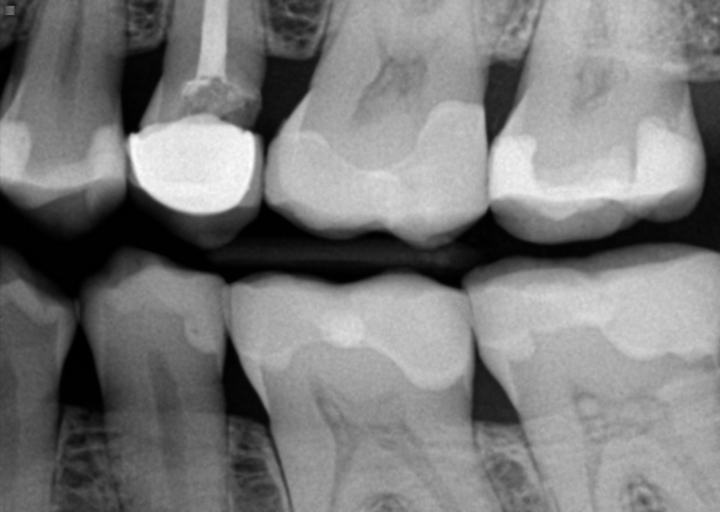

I have received conflicting opinions on a tooth: one dentist said it is cavity under the crown and treatment could be crown lengthening/dental implant while other dentist said there is no cavity, it's just ill fitted crown. Is this something we can see in Xray?

At minimum the crown needs to be replaced.  The distal (back) side of the tooth is radiolucent, which indicates there is an open space.  Usually, a space this large, indicates that there is recurrent caries present.  The only way to be certain is to remove the crown and diagnose it from there.  You do not want to leave it how it is, it will continue to worsen or if its an ill fitting crown, decay will develop.  Since the tooth has had a root canal, it will not hurt, however a secondary infection could develop.  Crown lengthening is only performed on a natural tooth.  If the tooth cannot be restored, an implant is the best option after the tooth is removed.